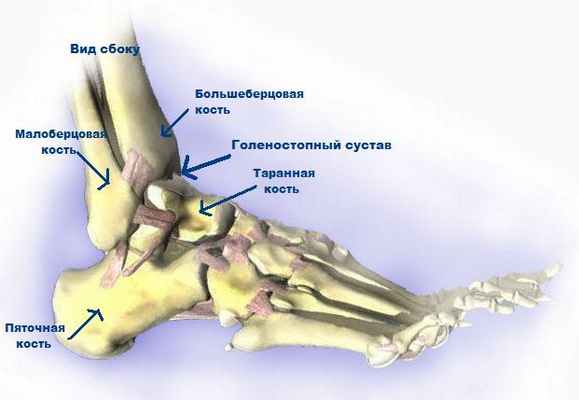

Лодыжка – двухсторонний костный отросток голени, состоящий из наружной (латеральной) и внутренней (медиальной) щиколотки.

Наружная щиколотка является дистальным окончанием малой берцовой кости, которая формирует голень. К внутренней прилегает большая берцовая кость.

Они проходят параллельно друг другу и образуют “угол”, расположенный на сочленении этих частей. Визуально лодыжка представляет собой костный бугорок с обеих сторон голеностопа.

Голеностопный сустав является достаточно сложным сочленением. Он образован соприкасающимися поверхностями таранной и большеберцовой кости, а по бокам стабилизируется двумя лодыжками. Эти костные выросты малоберцовой и большеберцовой костей расположены по бокам сочленения. Сочленение ежедневно испытывает серьезную нагрузку во время ходьбы, бега, прыжков, занятий спортом. Неправильная постановка ноги и выворот стопы кнаружи или внутри нередко становится причиной травмы.